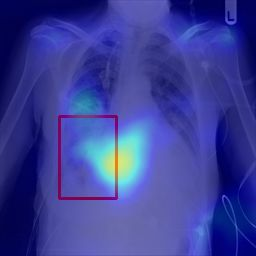

Deployments of artificial intelligence in medical diagnostics mandate not just accuracy and efficacy but also trust, emphasizing the need for explainability in machine decisions. The recent trend in automated medical image diagnostics leans towards the deployment of Transformer-based architectures, credited to their impressive capabilities. Since the self-attention feature of transformers contributes towards identifying crucial regions during the classification process, they enhance the trustability of the methods. However, the complex intricacies of these attention mechanisms may fall short of effectively pinpointing the regions of interest directly influencing AI decisions. Our research endeavors to innovate a unique attention block that underscores the correlation between 'regions' rather than 'pixels'. To address this challenge, we introduce an innovative system grounded in prototype learning, featuring an advanced self-attention mechanism that goes beyond conventional ad-hoc visual explanation techniques by offering comprehensible visual insights. A combined quantitative and qualitative methodological approach was used to demonstrate the effectiveness of the proposed method on the large-scale NIH chest X-ray dataset. Experimental results showed that our proposed method offers a promising direction for explainability, which can lead to the development of more trustable systems, which can facilitate easier and rapid adoption of such technology into routine clinics. The code is available at www.github.com/NUBagcilab/r2r_proto.